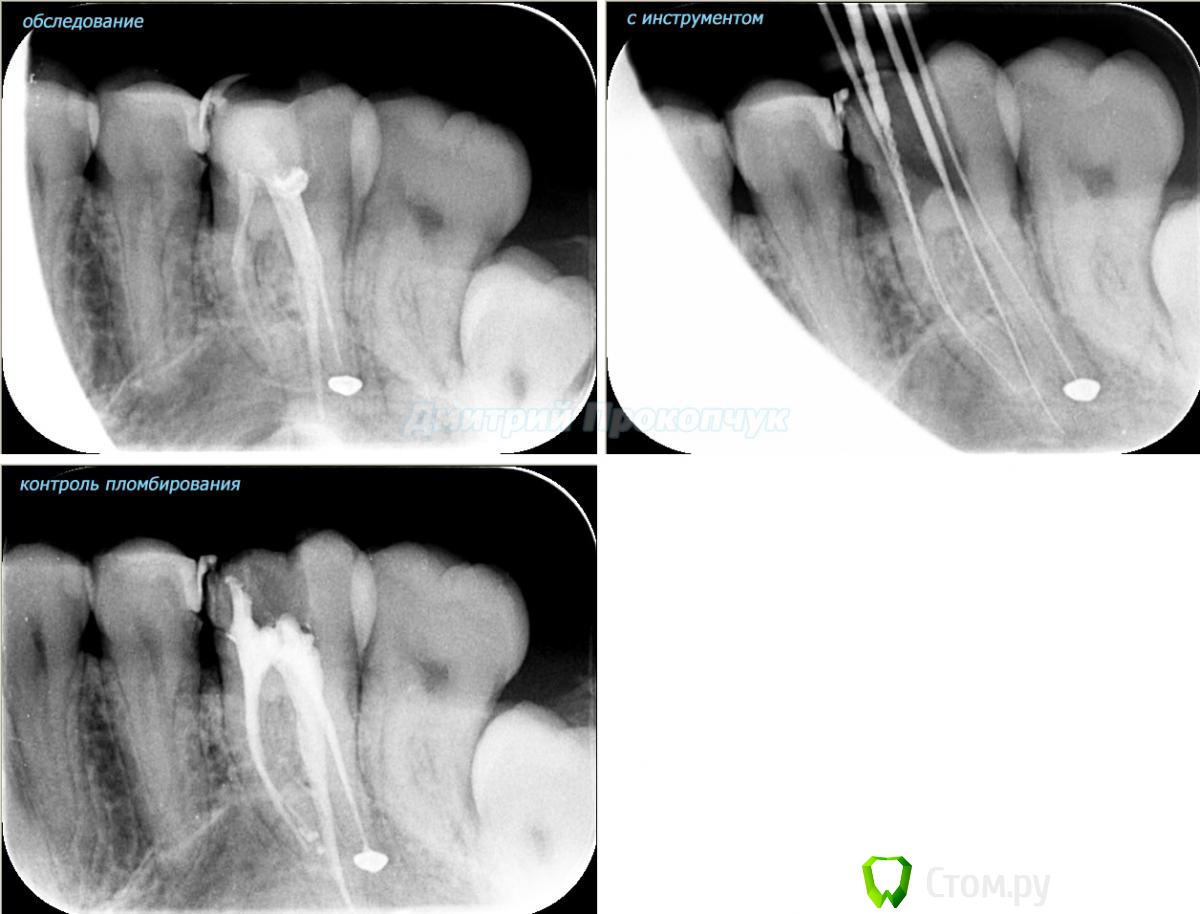

punkrat Опубликовано 16 сентября, 2014 Поделиться Опубликовано 16 сентября, 2014 Коллеги, тема , возможно, не имеет смысла просто приятная мне эндодонтия, сохранил с предыдущего места работы. Да, будь я проклят, я все знаю, НИГДЕ НЕТ КОФЕРА, на новом месте с этим норм. В общем если посчитаете, что я недостоин постить тут свои снимки, то так тому и быть, удалю тему.. 01. плановый ретрит 46ого и результат через 7 месяцев. Осложняющим моментом тут было то, что длина каналов была около 26 мм... 02. первичное эндо 34 (подготовка к ортопедии) + бонус - ретрит 35 03. ретрит 26 (подготовка к ортопедии) 04. ретрит 15, 16 (подготовка к ортопедии). основная сложность была в ретрите 15 - он был запломбирован термафилами, да еще снабжен свш... 05. ретрит 27 (подготовка к ортопедии). Ничего особенного, со временем посмотрим какова будет убыль этого совсем немаленького разрежения 06. ретрит 13. Разумеется пришлось выбивать вкладку, а потом еще попилить 3-4 миллиметра цемента, но, таки попилил куда нужно... 07. ретрит 17 (подготовка к ортопедии). В данном случае я, кажется, потратил больше времени на снятие литого моста, чем на лечение 17)) 08. ретрит 16 (подготовка к ортопедии). Снимка с инструментом нету, поскольку, визиограф сломался и его делал на пленку. 15 разумеется тоже перелечен... 09. плановый ретрит 16 10. первичное эндо 36, рядовой случай что дистальный щечный удалось найти не сразу, он был спрятан под нависающим дентиклем 11. ретрит 12, 11 (подготовка к ортопедии). Казалось бы, рядовой случай, если бы корневые каналы обоих зубов не были бы налухо забиты резорцин-формалиновой смесью... 12. ребенок 9ти лет, острый пульпит 46, попробовал оставить витальным. Пока полет нормальный, но даже если придется делать эндо в последствии, лучше когда оно будет сделано в более старшем возрасте... 13 Ссылка на комментарий